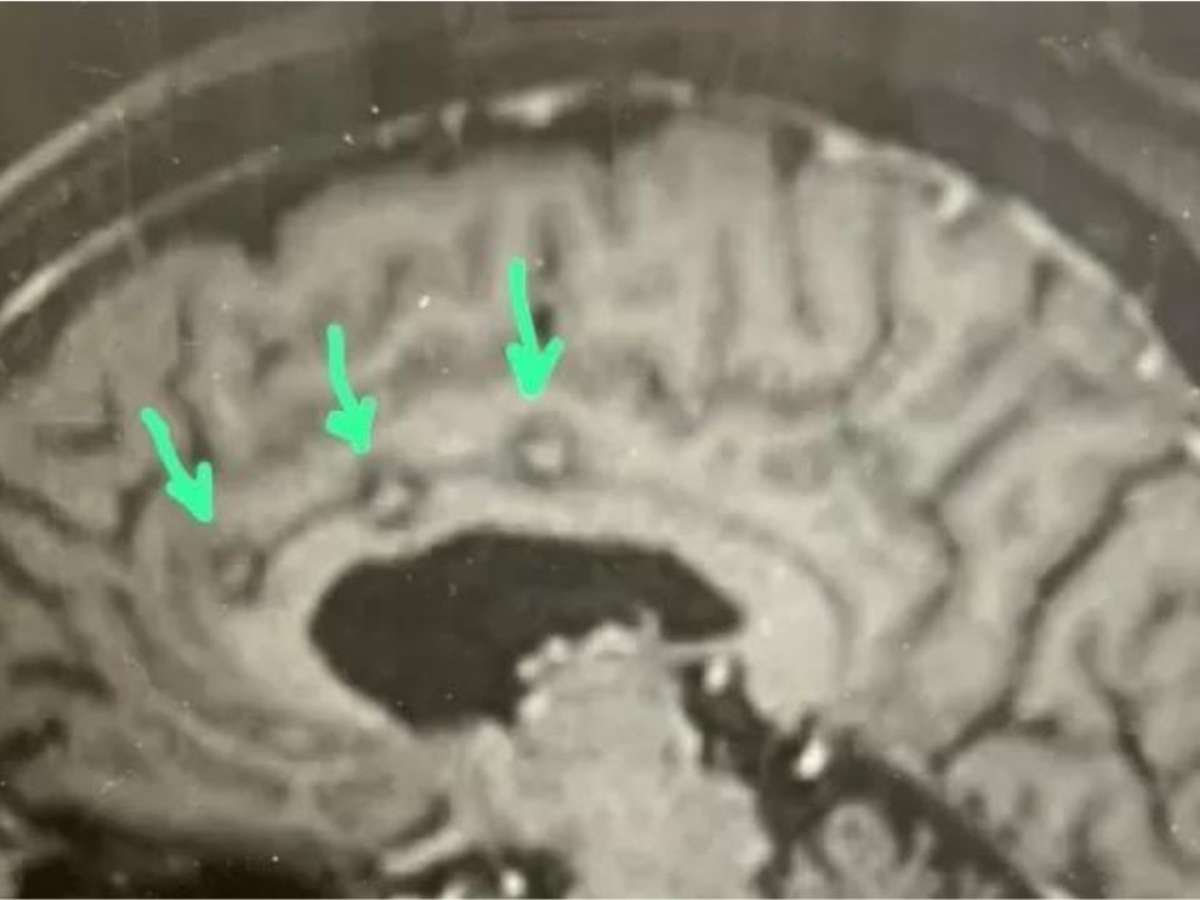

Para realizar o procedimento, o profissional faz uma pequena abertura no crânio, do tamanho de uma moeda, para passar os eletrodos. Dessa forma, o cirurgião os guia através de cortes específicos até atingirem o alvo final. O responsável pelo procedimento menciona que a cirurgia geralmente tem duração média de cerca de quatro horas.

"O paciente entra no centro cirúrgico para colocação de um arco que se fixa no crânio, com sedação e anestesia local. Depois segue para tomografia computadorizada do crânio. Depois da tomografia, puxa-se as imagens do sistema e fazemos a fusão das imagem com a ressonância do paciente", diz Wuilker.